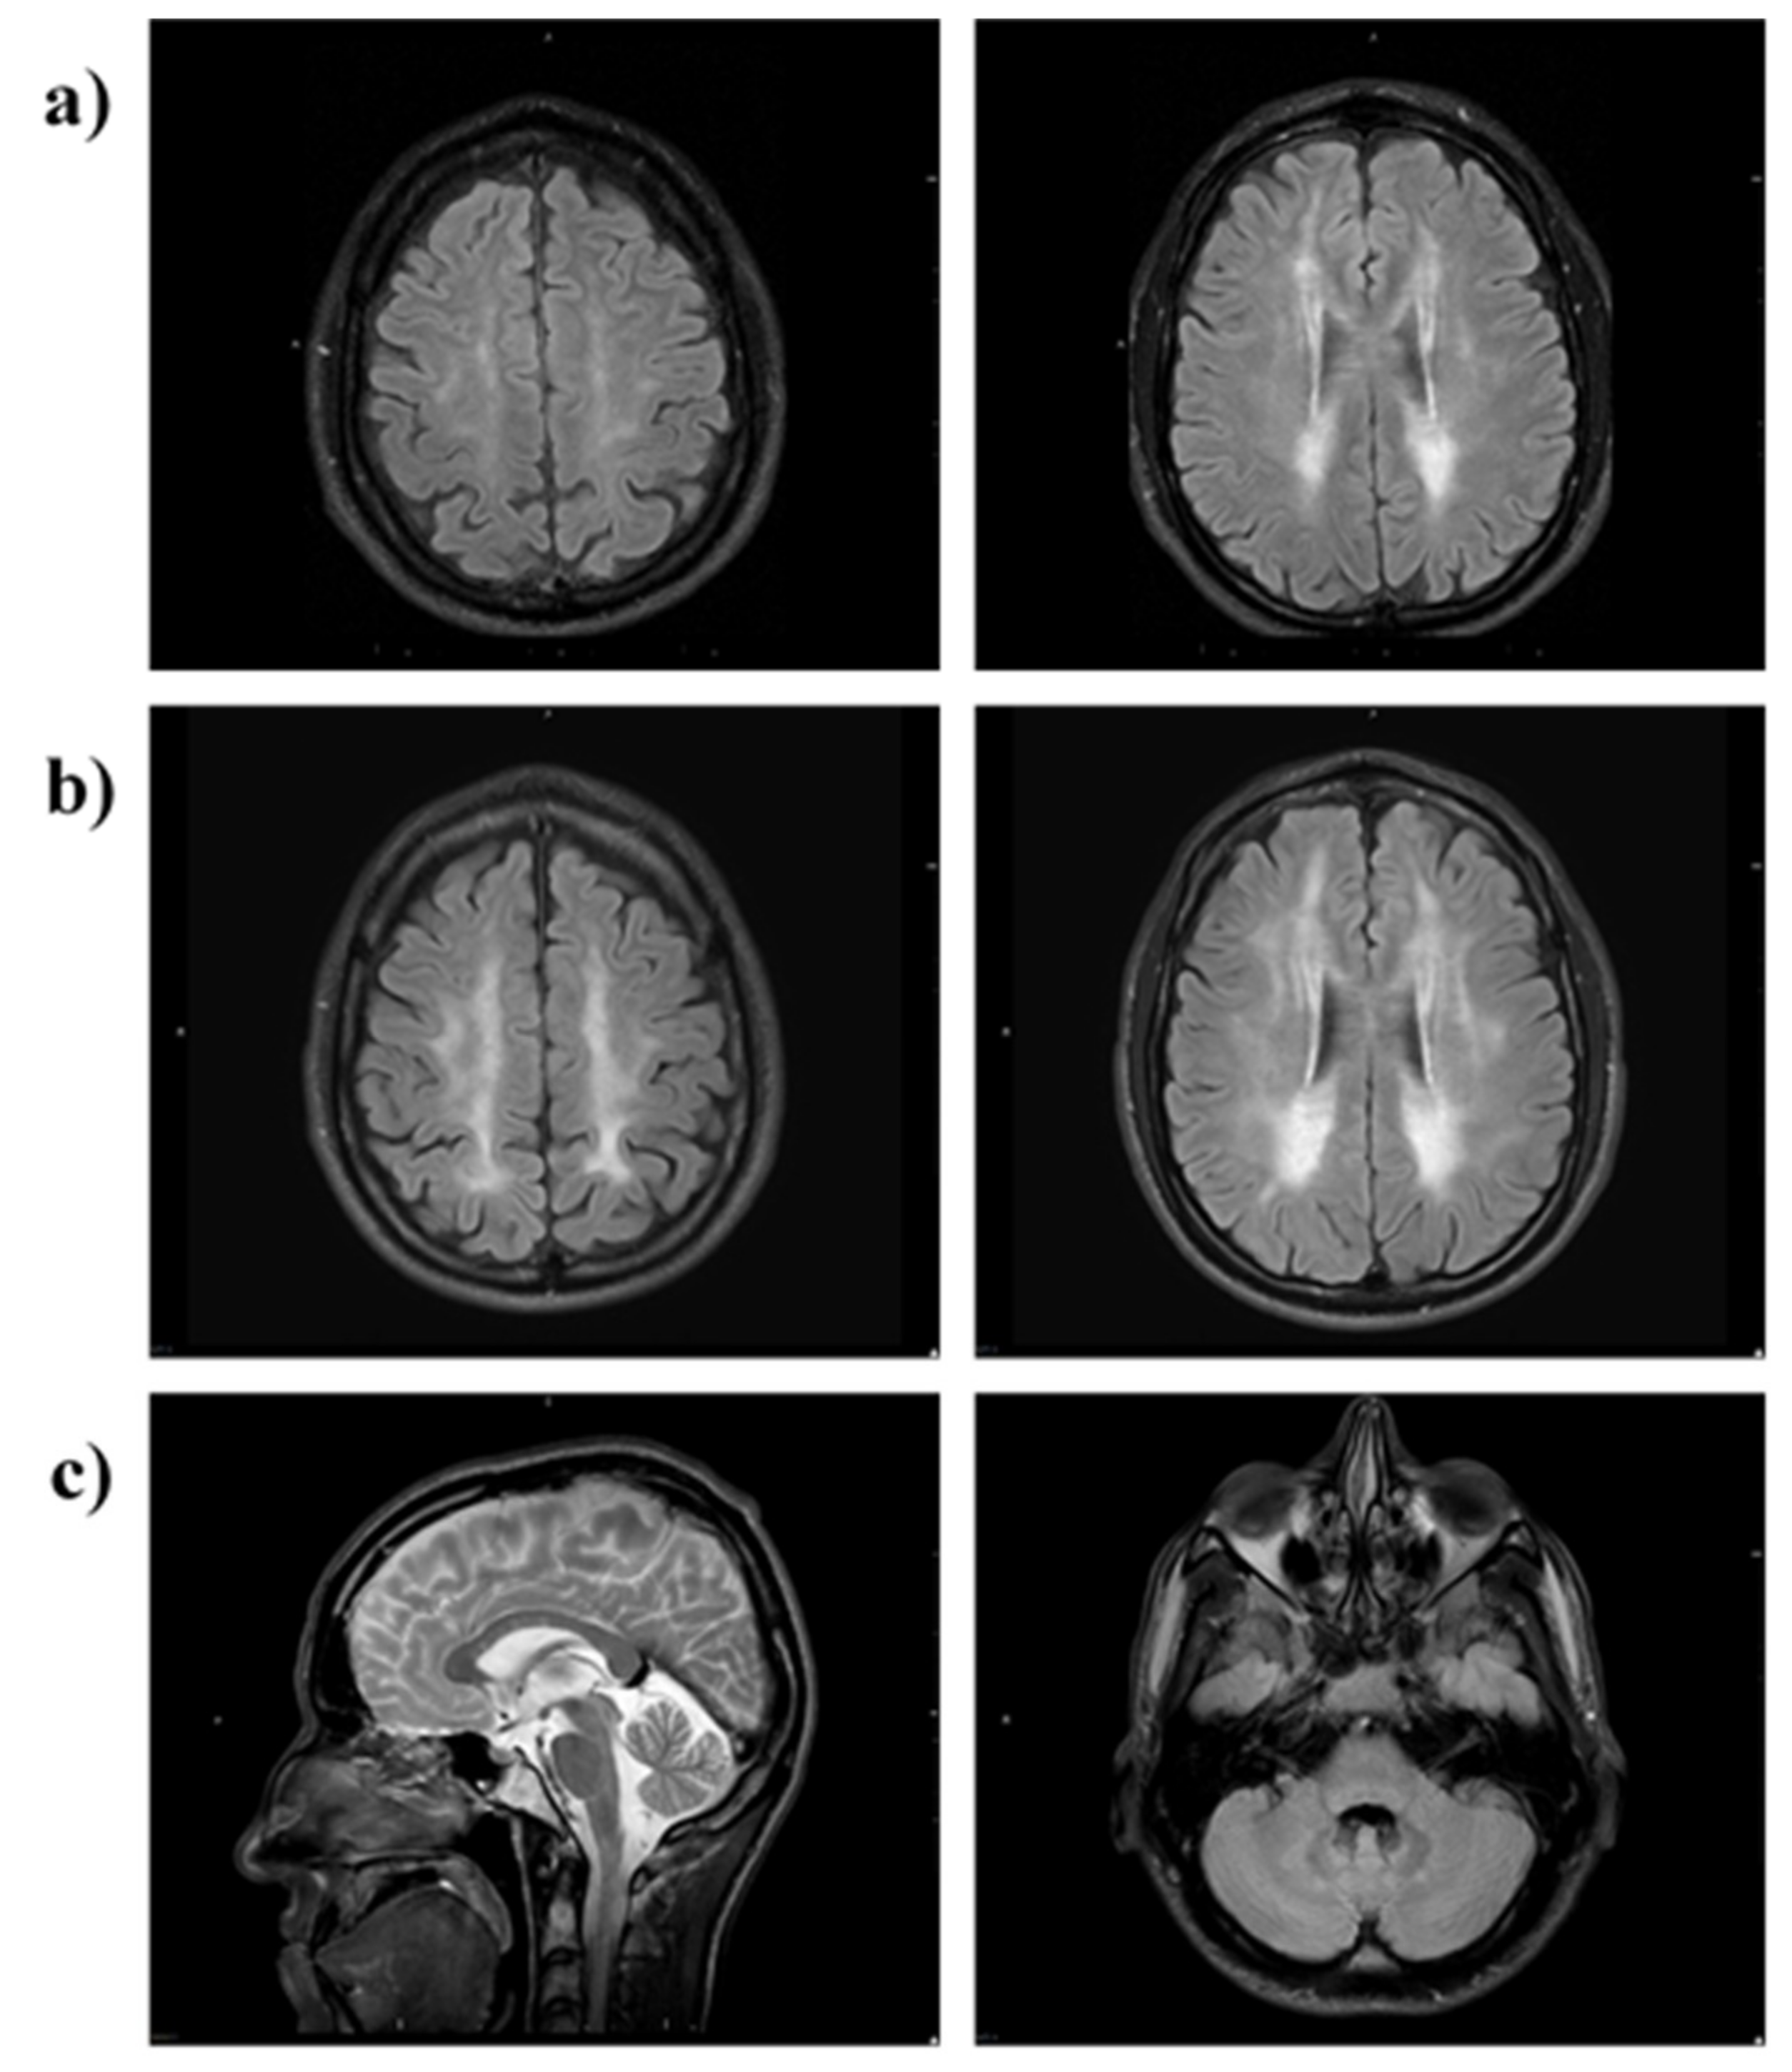

Brain MRI at month 28 of therapy showed almost symmetric, patchy areas of FLAIR and T2 hyperintensity in the cerebral periventricular, deep, and subcortical white matter (Figure 7a). A follow-up brain MRI at 63 months showed a progression of T2/FLAIR hyperintense cerebral white matter changes (Figure 7b). Relative sparing of the U fibres and the corpus callosum was noted (Figure 7c, left image). Infratentorially, there was minor symmetrical FLAIR hyperintense signal change in the cerebellar peridentate white matter (Figure 7c, right image).

Figure 7.

MRI brain of Patient 2. MRI (axial FLAIR) at (a) 28 months and (b) 63 months shows progression of T2/FLAIR hyperintense cerebral white matter changes (leukoencephalopathy). The scan at 28 months shows patchy involvement of cerebral periventricular, deep and subcortical white matter (a) which 35 months later is more confluent and extensive (b). There is relative sparing of the U-fibres and the corpus callosum (c, left image) and infratentorially there is minor symmetrical FLAIR hyperintensity in the cerebellar peridentate white matter (c, right image).

Leukoencephalopathy is a hallmark of MNGIE and in the majority of affected individuals, it is initially patchy, but it progressively becomes more diffuse, appearing as hypointense on T1- and hyperintense on T2- weighted images and in FLAIR and fast spin echo (FSE) T2 sequences (1). A follow-up brain MRI scan of Patient 2 showed a progression of T2/FLAIR hyperintense cerebral white matter changes. Therefore, EE-TP therapy was not able to halt the progression of the leukoencephalopathy. However, it is not known whether therapy was able slow down the rate of progression. An additional consideration of the extent and distribution of leukoencephalopathy is not distinctly correlated with age and the clinical phenotype [33]. More extensive MRI studies of untreated and treated patients with MNGIE are required to establish whether the leukoencephalopathy can be reversed. Post mortem histopathological studies of brains have shown the presence of albumin in the cytoplasm of reactive astrocytes in patients with MNGIE, as compared to age-matched healthy individuals, suggesting functional blood brain barrier alterations and consequent vasogenic oedema as a cause of leukoencephalopathy in MNGIE [34]. Furthermore, mild perivascular gliosis was also observed in immunohistochemical analyses [35]. Thymidine phosphorylase is also referred to as gliostatin, and it has been shown to exert strong inhibitory effects on glial cells and neurotrophic effects on cortical neurons [36,37,38]. Therefore, the leukoencephalopathy in MNGIE may be a consequence of the absence of the inhibitory activity of thymidine phosphorylase, rather than its catalytic activity. If this is the case, the white matter aspect of MNGIE will not be responsive to treatment strategies, which reduce or remove the pathological deoxyribonucleosides.